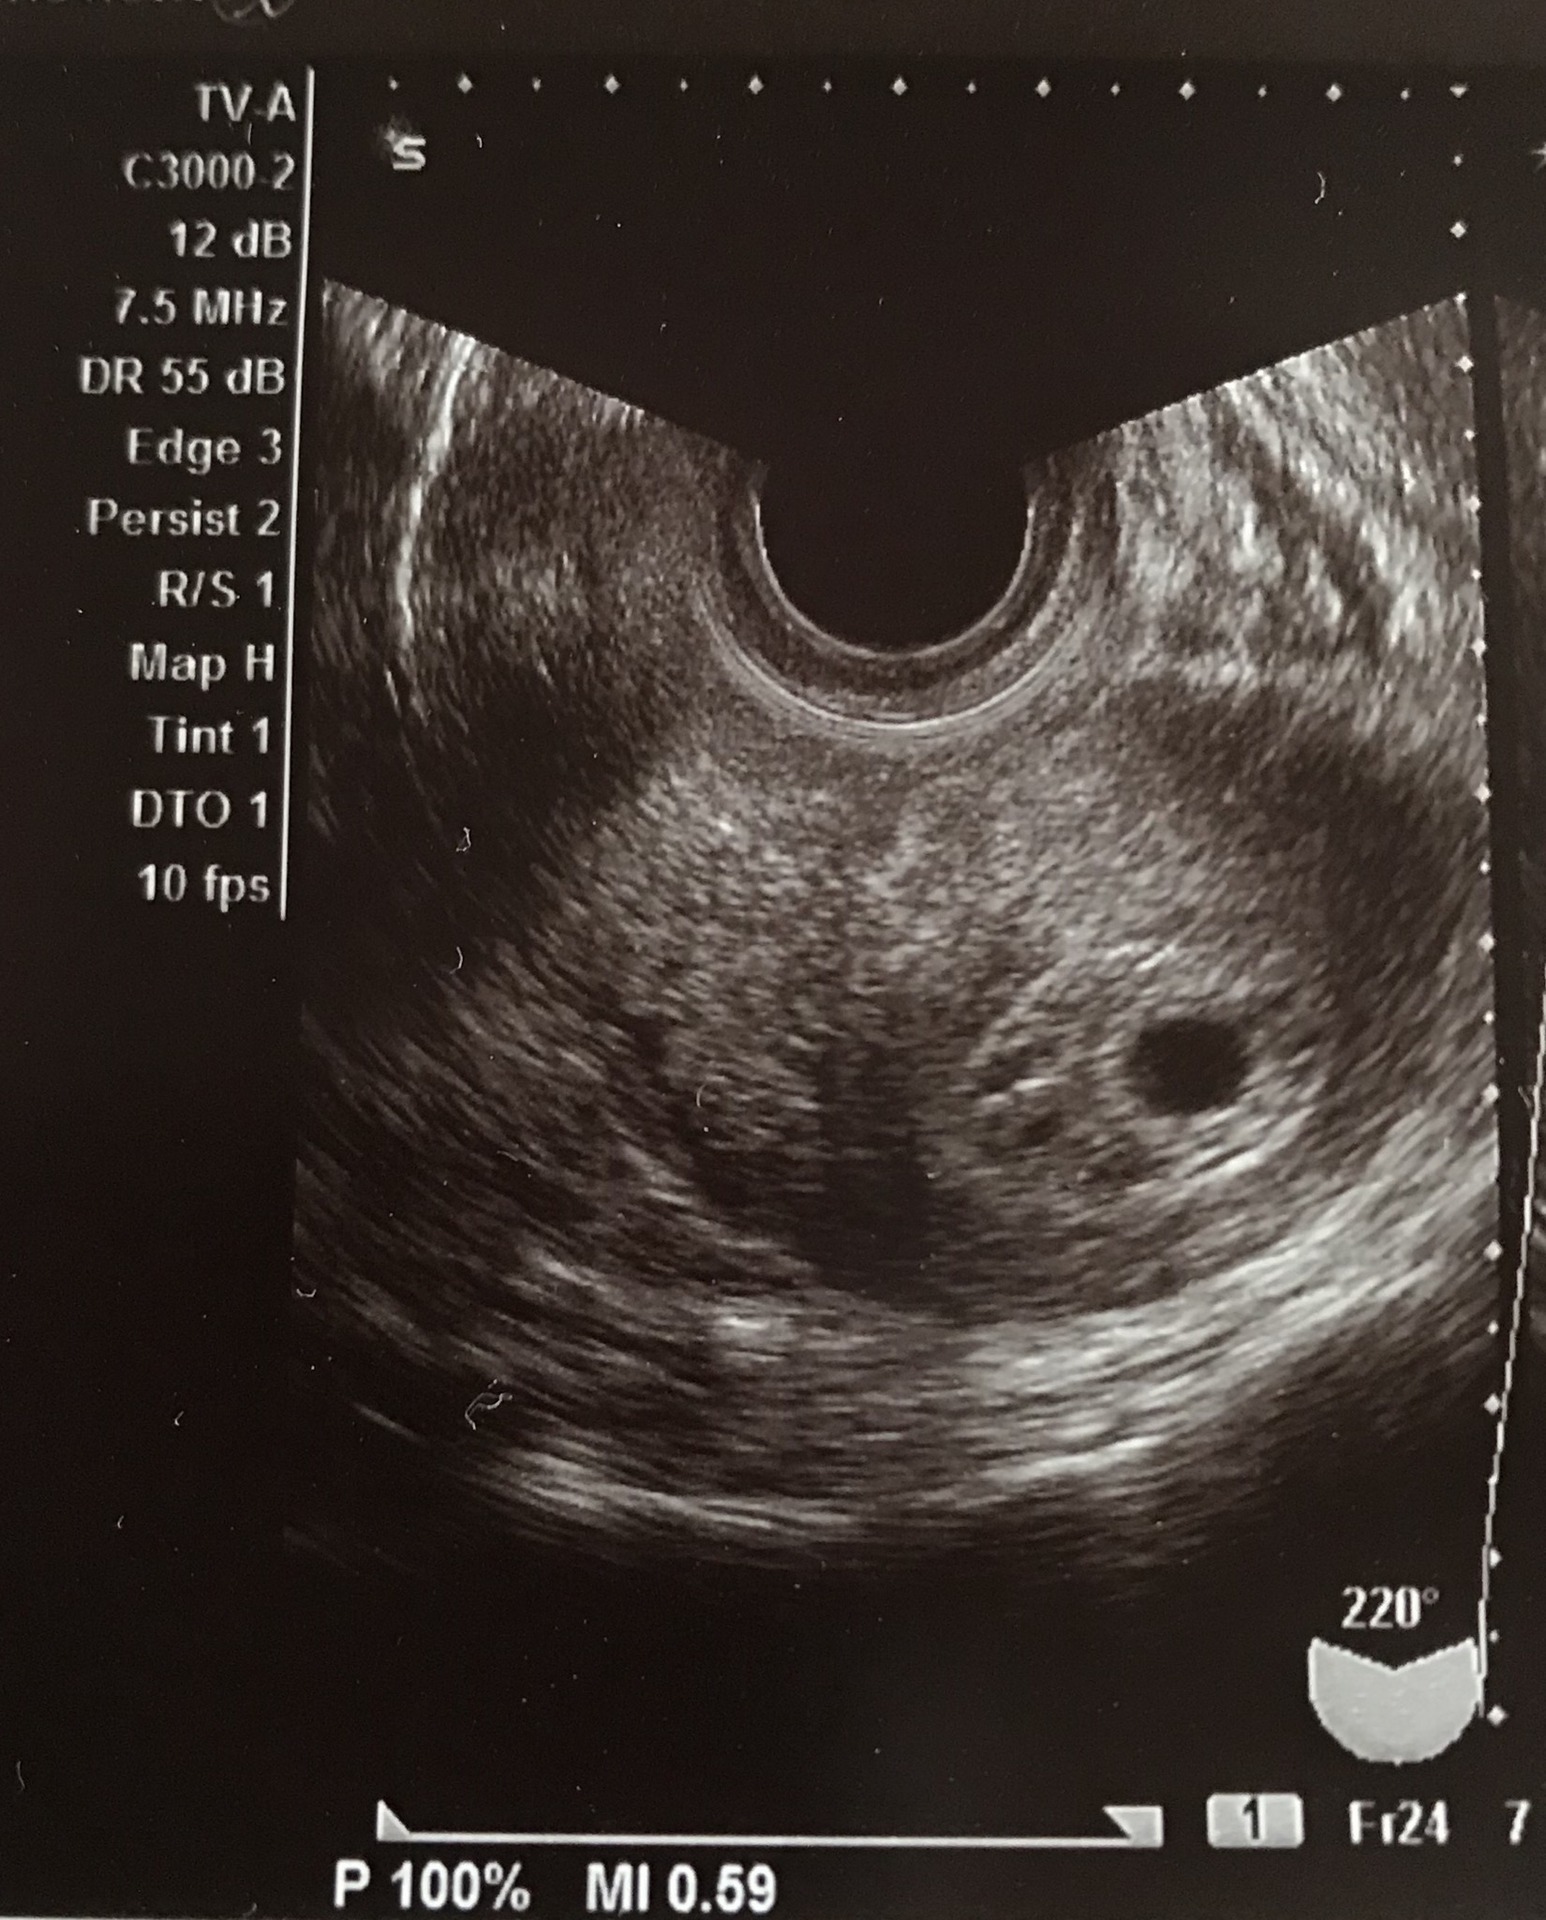

8 稽留流産の診断 日本産婦人科医会

8 稽留流産の診断 日本産婦人科医会

8 稽留流産の診断 日本産婦人科医会